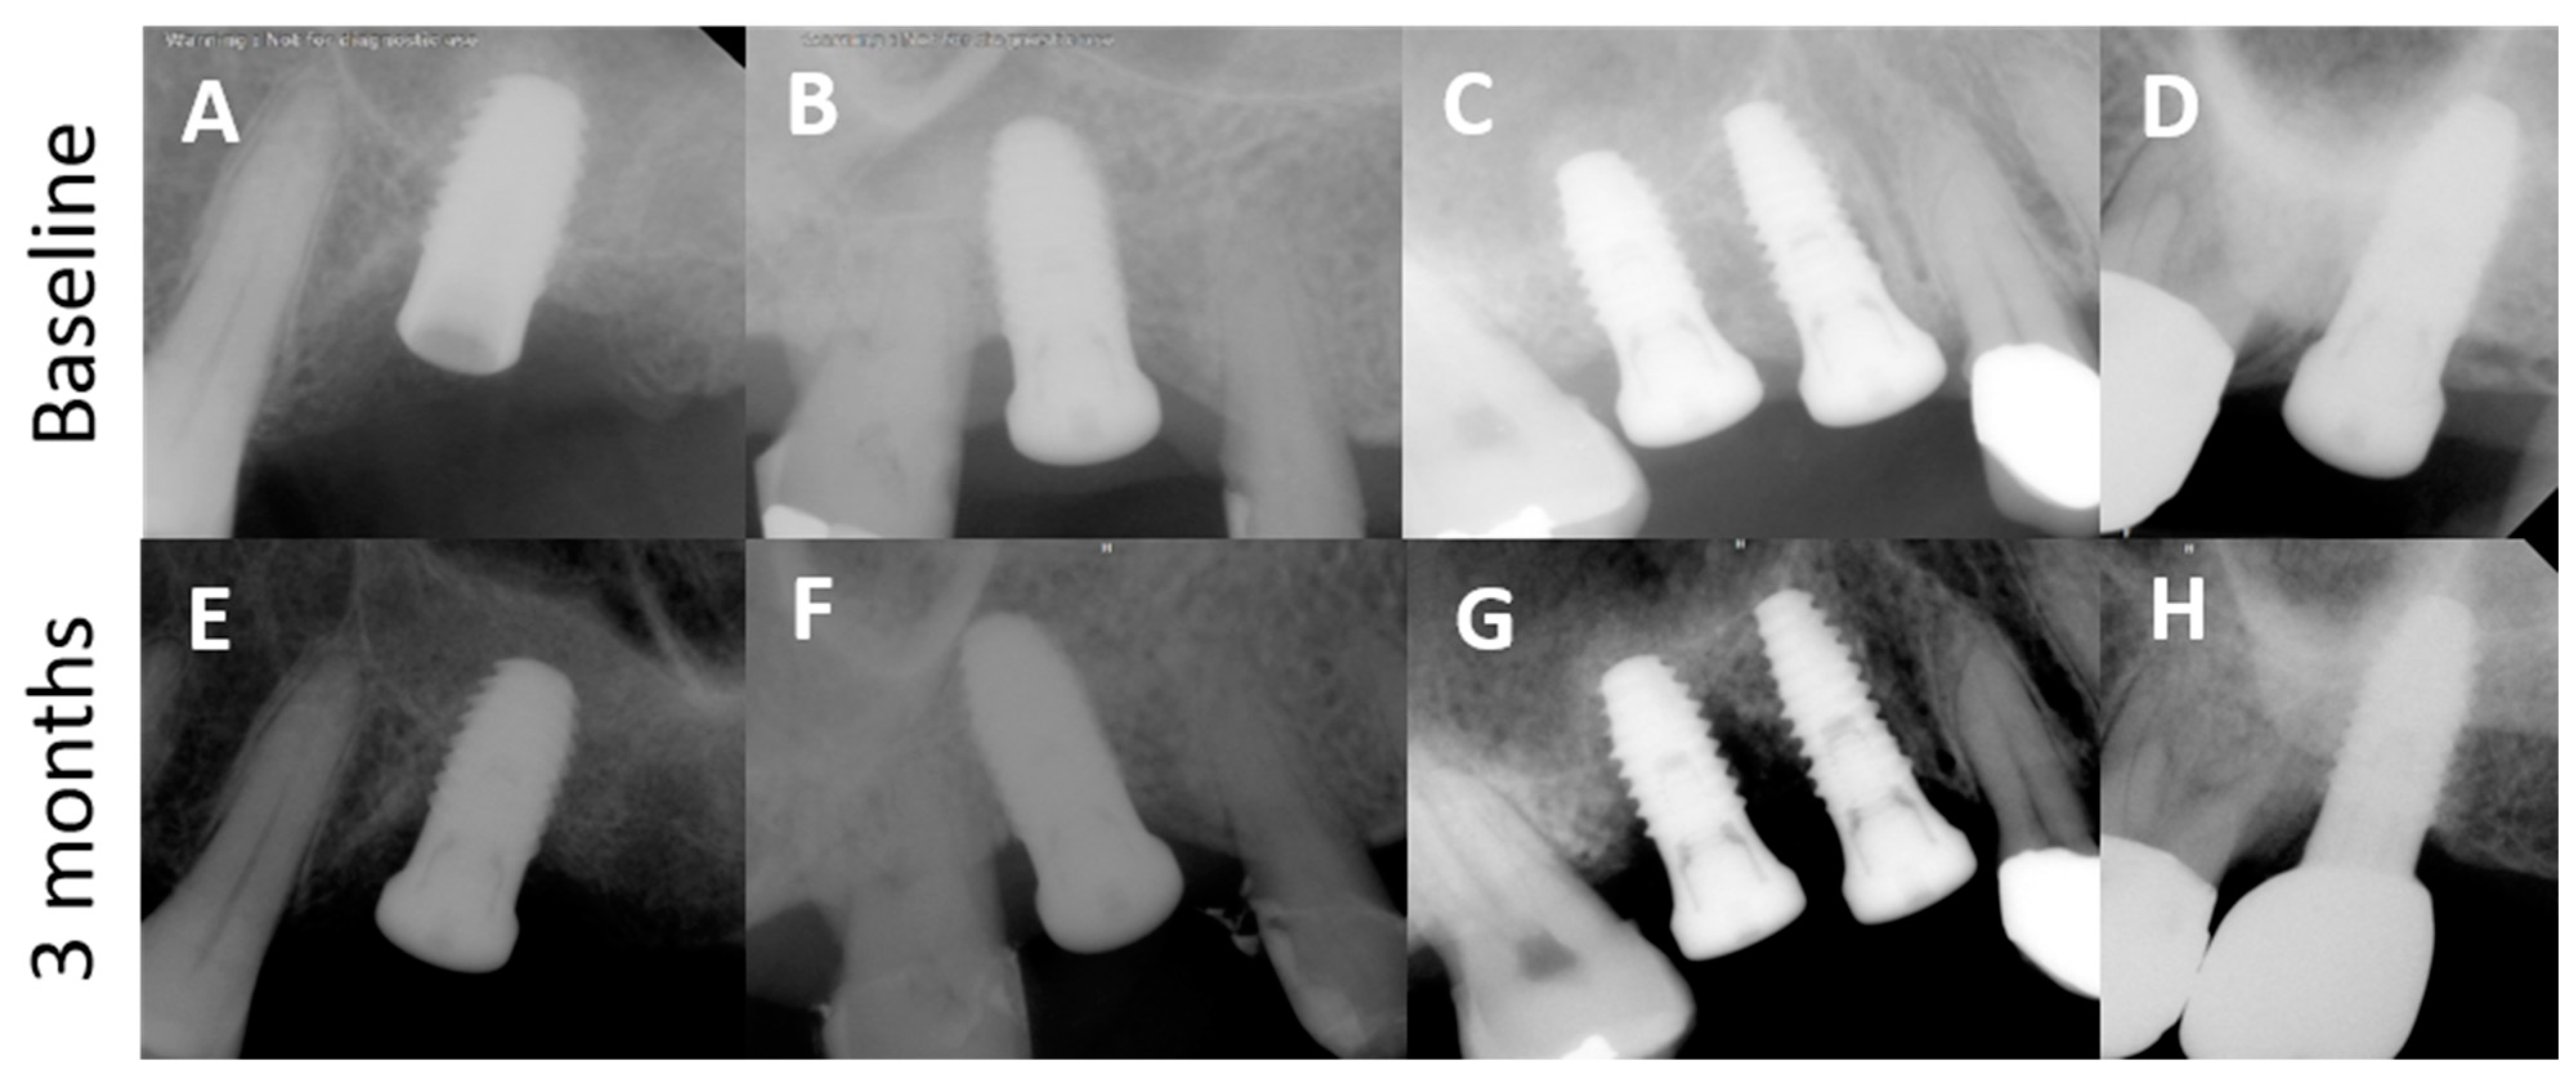

3.2. Radiographic Observation

3.3. Accuracy of Implant Placement Using the VARO Guide